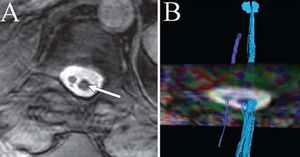

Tractography for spinal dysraphism exemplified in a 53-year-old women with diastematomyelia. Panel A shows two hemicords on an axial T2-weighted image at L3 level, with the larger cord on left (arrow). Panel B shows tractography of the two hemicords. The axial image represents color-coded FA map. Larger tract (light blue) is composed of greater number of individual fiber tracts and corresponds to larger (left) hemicord. (Filippi et al., Eur Radiol, 2010)